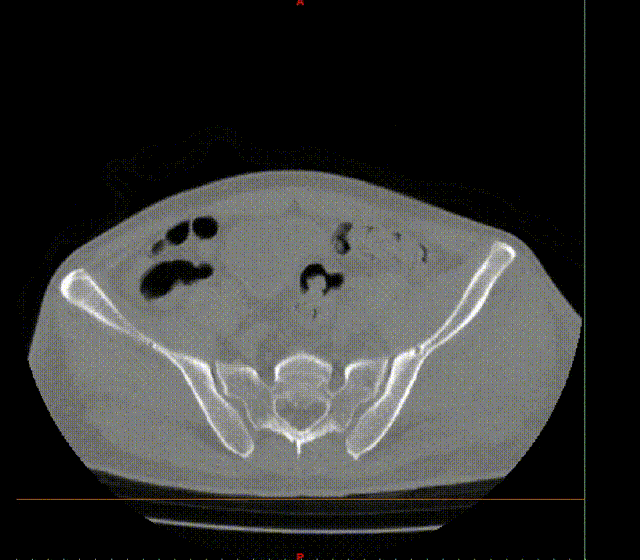

张洪彬医生对患者骨盆三维CT进行了术前虚拟仿真,辅助术者规划骨折复位过程及通道螺钉的置入长度、角度及方向。在患者伤后2周内,由刘利主任主刀,采取单一Kocher-Langenbeck 入路手术入路,术中仔细对坐骨神经及旋股内侧动脉进行了保护,降低了远期发生神经损伤及股骨头缺血性坏死发生风险,完成复位后,应用两块重建钢板及一枚通道螺钉就完成了复杂骨折的固定。术后复查DR及CT骨折复位理想,内固定位置满意,没有发生螺钉进入关节腔的情况。患者得到了早期功能康复锻炼的有利条件。患者现已顺利出院。